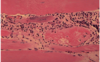

A 49-year-old African American woman presents with gradual onset and fluctuation of weakness over the past six months. The patient first noticed difficulty in walking up and down stairs, which progressively worsened and came to involve combing her hair in the morning. The patient reports no associated pain with these movements. Review of systems is significant for shortness of breath with physical exertion out of proportion to her normal level. Osteopathic examination shows that ribs 2-5 minimally expand with inspiration, although they have adequate recoil with expiration. A muscle biopsy was obtained as shown in the exhibit. The most likely cause of this patient’s weakness is

polymyositis

This picture shows the degeneration of muscle fibers caused by the Anti-Jo-1 antibodies in polymyositis. In polymyositis, the cellular infiltrate is predominantly within the fascicle with inflammatory cells invading individual muscle fibers. Histopathology shows focal endomysial infiltration by CD8+ T lymphocytes and macrophages, capillary obliteration, endothelial cell damage, and increased amounts of connective tissue dueto muscle fiber necrosis